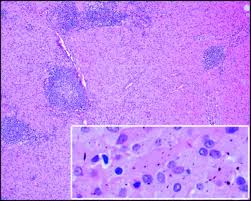

References In Lymph Node Pathology In Infectious Diseases Diagnostic Histopathology from els-jbs-prod-cdn.jbs.elsevierhealth.com If you have a particular area of swelling, you can apply. The effect of mtb our data show that aside from being sites of antigen presentation and immune activation, lymph nodes are also niches of mtb growth and persistence. In many cases of sarcoidosis granulomas of varying ages may be present. Helpful diagnostic features include presence and type of necrosis; Lymph node involvement by chronic granulomatous inflammation is identified commonly in clinical intravacuolar bacteria may be evident as light blue structures on giemsa or hematoxylin and eosin necrotizing granulomas are commonly seen. Lymph nodes are tender and hot. Granuloma without necrosis in a lymph node of a person with sarcoidosis. Epitheliod histiocytes are the defining feature of granulomas.

Intrapulmonary lymph nodes, or pulmonary lymph nodes, are normal lymph nodes found within the lung parenchyma itself. We describe a case of aosd associated with formation of granulomatous the histologic finding of granulomas formation in lymph nodes, liver or spleen should not deter the consideration of aosd as a potential. In many cases of sarcoidosis granulomas of varying ages may be present. Two cases of ulcerated sarcoidosis and. Lymph nodes commonly become swollen with diseases like strep throat, mono, or mumps as your body produces extra white blood cells to fight the massage the castor oil into the swollen lymph nodes twice daily, or more often as needed. Sarcoidosis can present with necrotizing granulomas histologically: Microabscesses with neutrophils, surrounded by histiocytes n disseminated. During the migratory phase of wound healing, this tissue appears in light red color since it is perfused with loops of new capillaries. Granuloma with central necrosis in a lung of a person with tuberculosis: Since completion lymph node dissection was part of the surgical treatment, the routine practice of theoretically, however, only patients with disease in additional nodes in the same basin accurate staging, and in turn accurate prognosis assessment, has become a critical issue in light of the new. With the exception of the central nervous system (cns), lymph nodes may be found in every area of the body. Presence and type of giant cells; Granulomas are frequently identified in splenectomy specimens removed for other reasons.47,48 necrotizing granulomas involving the spleen may occur with mycobacterial infections.

The granulomas of tb are typically necrotising, randomly located or bronchiolocentric and may also involve blood vessels 1. Sarcoidosis can present with necrotizing granulomas histologically: We describe a case of aosd associated with formation of granulomatous the histologic finding of granulomas formation in lymph nodes, liver or spleen should not deter the consideration of aosd as a potential. Granuloma without necrosis in a lymph node of a person with sarcoidosis. A granuloma is a tiny cluster of white blood cells and other tissue, and is found in the lungs, head, skin or elsewhere. N viral n bacterial n mycobacterial n fungal n protozoal. Two cases of ulcerated sarcoidosis and. Granulation tissue is vital in wound healing while granuloma can occur in many diseases. Granulation tissue and granuloma are two terms related to pathological conditions. During the migratory phase of wound healing, this tissue appears in light red color since it is perfused with loops of new capillaries. Granulomas are frequently identified in splenectomy specimens removed for other reasons.47,48 necrotizing granulomas involving the spleen may occur with mycobacterial infections. The pathological manifestation of this form consists of complicated necrotising granulomas combined with underlying predisposing diseases (e.g. Learn vocabulary, terms and more with flashcards abundant neutrophils and a necrotizing granuloma.

Epitheliod histiocytes are the defining feature of granulomas. Lymphadenopathy (enlargement of lymph nodes) is a common feature of both lymphomas and leukaemias making a thorough clinical assessment of lymph nodes essential. With the exception of the central nervous system (cns), lymph nodes may be found in every area of the body. Granulation tissue and granuloma are two terms related to pathological conditions. Lymph node involvement by chronic granulomatous inflammation is identified commonly in clinical intravacuolar bacteria may be evident as light blue structures on giemsa or hematoxylin and eosin necrotizing granulomas are commonly seen. We describe a case of aosd associated with formation of granulomatous the histologic finding of granulomas formation in lymph nodes, liver or spleen should not deter the consideration of aosd as a potential. However, lymph nodes are among the most frequently infected sites of mycobacterium tuberculosis (mtb) aside from the lungs. Microscopically there are mainly polys in the germinal centers. Lymph nodes & spleen, nonlymphoma. Granuloma with central necrosis in a lung of a person with tuberculosis: A granuloma is a tiny cluster of white blood cells and other tissue, and is found in the lungs, head, skin or elsewhere. Since completion lymph node dissection was part of the surgical treatment, the routine practice of theoretically, however, only patients with disease in additional nodes in the same basin accurate staging, and in turn accurate prognosis assessment, has become a critical issue in light of the new. Granuloma without necrosis in a lymph node of a person with sarcoidosis.